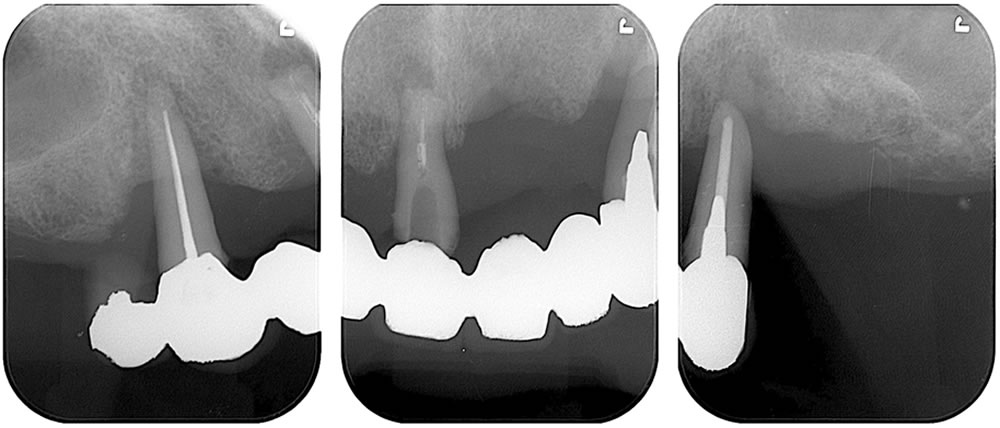

レントゲン検査

レントゲン精査を実施。上顎残存歯は歯を支える骨がほとんどなくなっており、保存するのは不可能な状態(重度歯周炎)と診断しました。

術前と比較して咬み合わせが安定しました。歯の傾斜も改善され、審美的にも患者さまにご満足いただけました。下顎は補綴前に必要部位の根管治療を行っています。X線写真上、下顎右4番の根尖病変は縮小傾向を示しています。